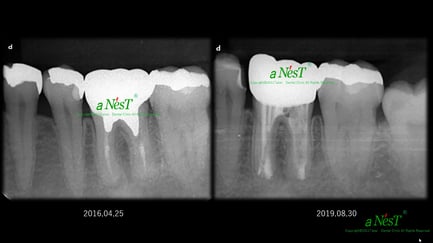

他院で抜歯と診断された症例です。友人の歯科医師の紹介で遠方から通院されました。初診時(左図)には、楔印で示すように、歯の根の先に黒い影が明瞭に写っています。が治療開始から8ケ月後(右図)では、黒い影は消えたり縮小しています。

歯の根の先の黒い影も消え(左図)、(手前は完全に消えていないが、完全な縮小傾向と症状がない)たので、クラウンを装着するための型採りをします。

右図の楔印は破折線です。破折線は特殊な方法で修復しています。

治療期間:約1年

治療回数:10回(1回/月)

治療費:29万円(根管治療+支台築造+セラミックス・クラウン)※毎回の処置料は別途